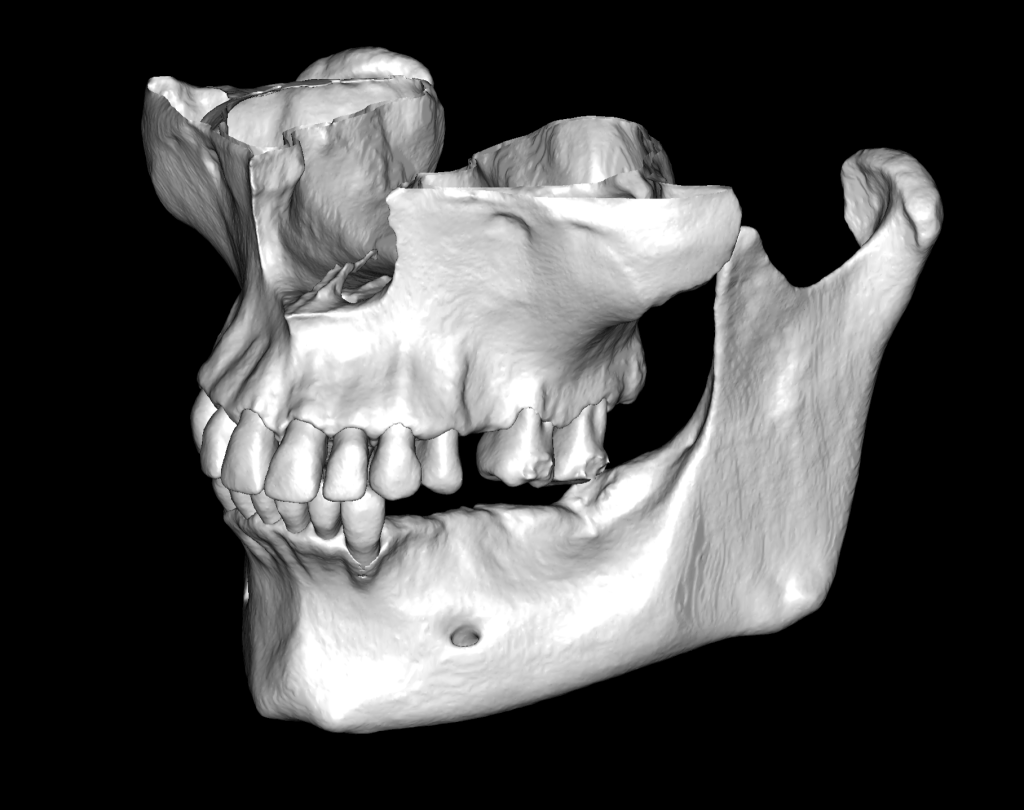

Fully automatic segmentation and creation of 3D models from DICOM files allows you to select individual structures for printing models on a 3D printer

Based on these models, stereolithographic models were produced to plan the placement of the titanium mesh and ensure its accurate fit